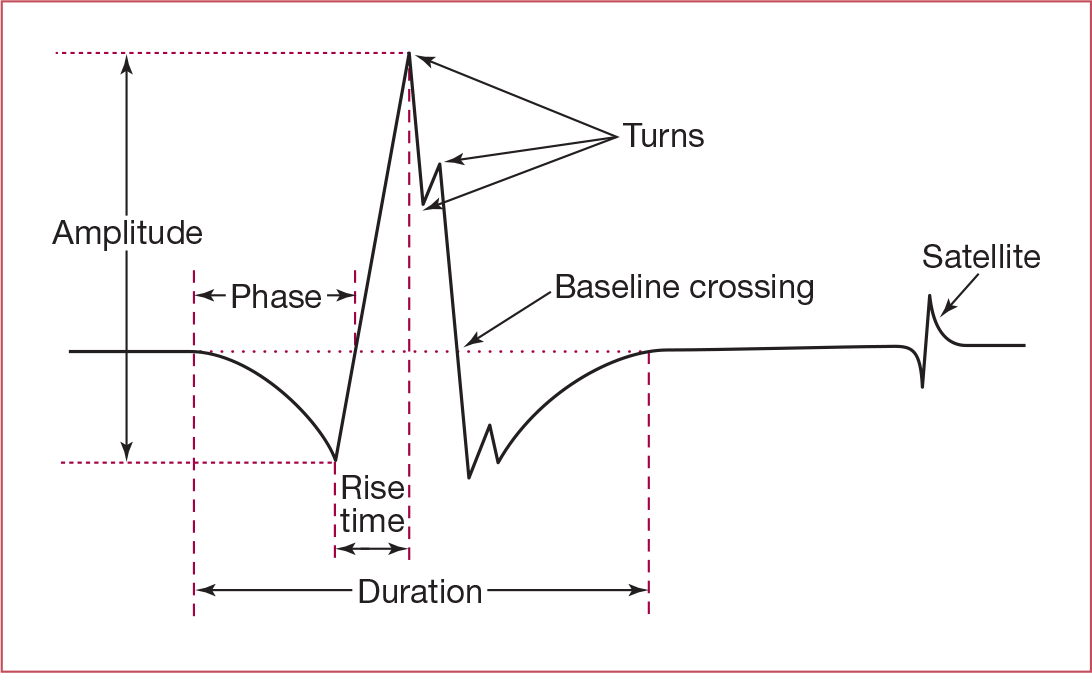

Normal duration, amplitude, and phases of a motor unit action potential?

- Duration: 5 - 15 ms

- Amplitude: up to 2 mV

- Phases: 2-4 (equal to # of baseline crossings + 1)